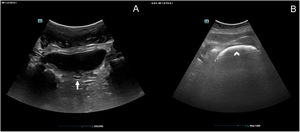

During hospitalization, she presented diarrhea (over 10 stools per day), whereby feces samples were taken for a polymerase chain reaction based fecal pathogen panel, with negative results. In this context, abdominal radiography was performed not showing relevant abnormalities besides feces in the recto-sigmoid area. As a complementary tool for enhanced physical examination, abdominal sonography was performed showing signs of fecal impaction, hence, facilitating the diagnosis (Fig. 1B). A manual extraction was performed, showing a decrease in the diameter of the rectum ampulla. Furthermore, an abdominal computed tomography (CT) was performed 3 days later, to further investigate the weight loss which confirmed fecal impaction in the rectum as well as copious feces through the colon. Unfortunately, the patient's clinical situation deteriorated and eventually died with bloody stools, probably due to stercoral colitis.

Few studies have examined the use of sonography in the evaluation of constipation and fecal impaction. To perform the exam, the patient lies in a supine position, and the curvilinear or linear probe is placed in the abdomen, following a “mowing the lawn” scanning technique. The signs described in the literature, are a hyperechoic area shaped like a half-moon for fecal retention in the rectum with acoustic shadow for hard stool retention3 and increased rectum diameter (Fig. 1B). It has been shown that 92.9% of elder patients with an acoustic shadow on the crescent shape hyperechoic area had hard stools.4,5